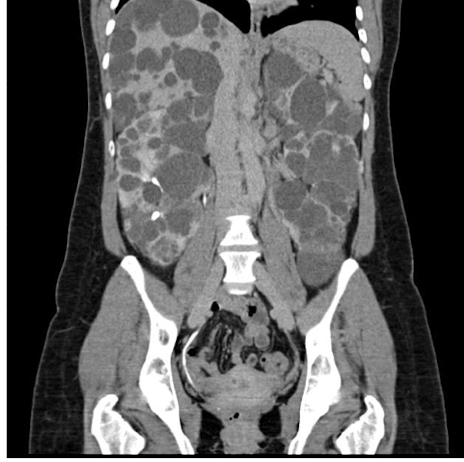

What is this and what type of scan

Polycystic kidney disease, CT scan